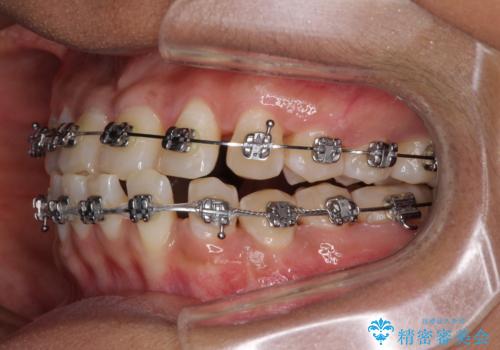

反対咬合の改善 途中で出産をしながらワイヤー矯正

- 矯正装置

- メタルブラケット

- 前歯の隙間と反対咬合を気にして来院された患者様です。

マウスピース矯正も提案しましたが、しっかりと使用する自信がないとのことで、ワイヤー装置により矯正治療を行うこととしました。

咬合力が強く、反対咬合の改善に時間がかかりましたが、その後はスムーズに進めることができました。